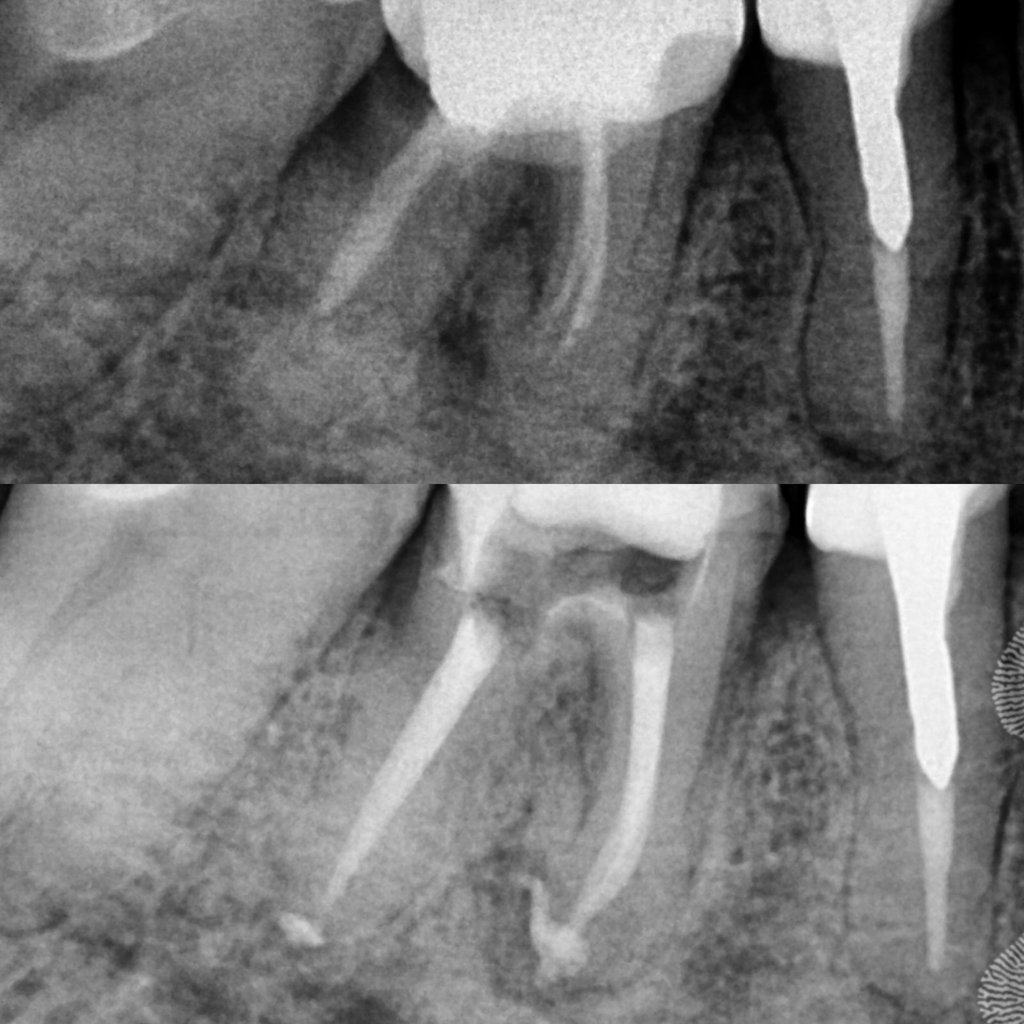

Em alguns casos, a necessidade de tratamento de canal é identificada em exames radiográficos, mesmo antes de o paciente sentir dor.

As radiografias periódicas podem revelar lesões na ponta da raiz, indicando um foco de infecção que precisa ser tratado.

Nesses casos, apenas o tratamento endodôntico é capaz de eliminar o problema e restaurar a saúde do dente.

Galeria

Na odontologia, cada sorriso é único e o resultado final depende de fatores biológicos individuais. Imagens clínicas não constituem promessa de resultado. Planejamento técnico e diagnóstico são fundamentais para o sucesso do tratamento."